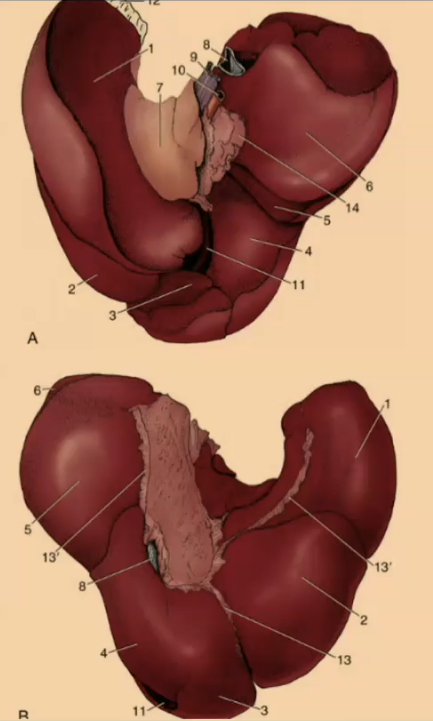

How many lobes are there to the liver?

4

What are the 4 lobes of the liver?

Left, Quadrate, Right, Caudate

#2?

Medial

#1?

Lateral

#3?

Quadrate

#4?

Medial

#5

Lateral

#6 & #7

Caudate